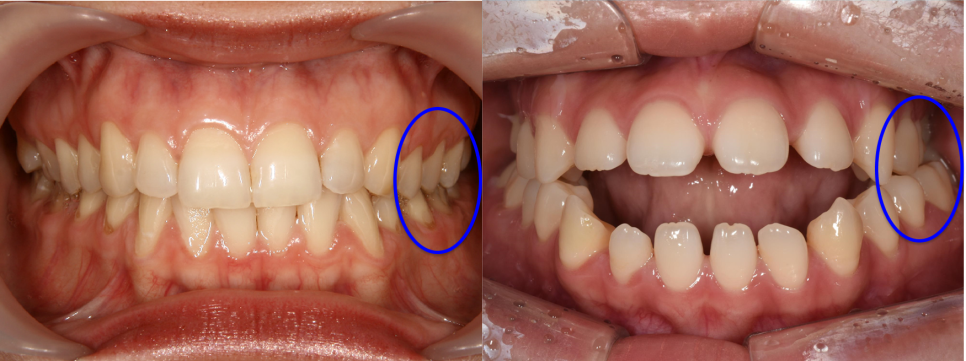

치료 전후 비교사진

환자분께서 느끼시는 불편함은 세라믹치과의 정밀 검사 결과에서도 명확히 확인되었습니다. 어금니를 물어도 앞니가 다물어지지 않는 개방교합과 안면 비대칭, 그리고 미약한 돌출입 증상도 있었습니다.

구강 내부 상황도 복잡했습니다. 왼쪽 위 치아가 하나 결손된 상태였고, 그 공간 때문에 치아들이 전체적으로 벌어져 있었습니다. 대학병원에서 왜 수술을 권유했는지 충분히 이해가 갈 만큼 복합적인 문제들이 얽혀 있는 케이스였습니다.

(좌) 어금니가 다물어져있는데도 앞니는 물리지 않고 떠 있다. (우)환자분 기준 "왼쪽"에는 어금니가 하나밖에 없다